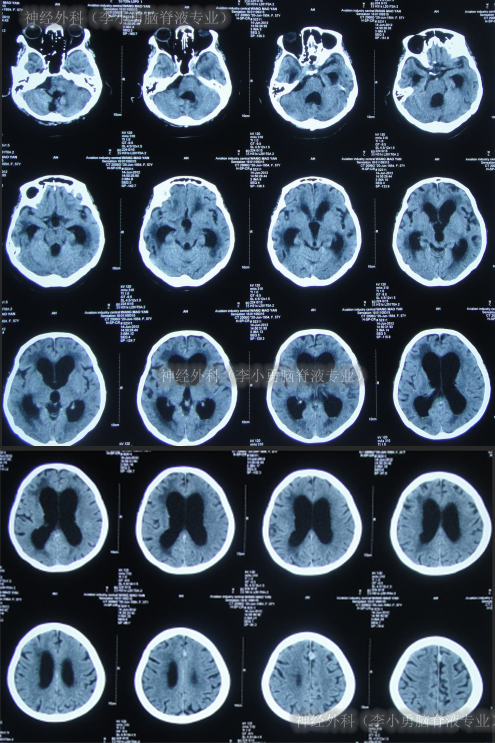

又过2月后即2011年10月14日,夜里2点起夜时突然站不稳,再次出现头昏,呕吐频繁,四肢无力,2011年10月17日第2次就诊于第2家医院:呼和浩特市某医院神经内科住院治疗,行头颅MRI(图-1)认为“末梢神经脱髓鞘病变,考虑为格林巴利综合征,轻度脑积水”。

图-1:2011年11月17日头颅核磁